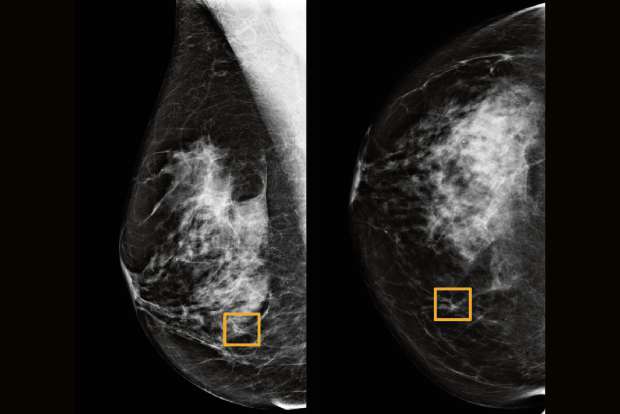

Study finds how new technique transform breast cancer detection

Mammography is a useful screening tool for early identification of breast cancer; however, its sensitivity is lowered in dense tissue, caused by the...